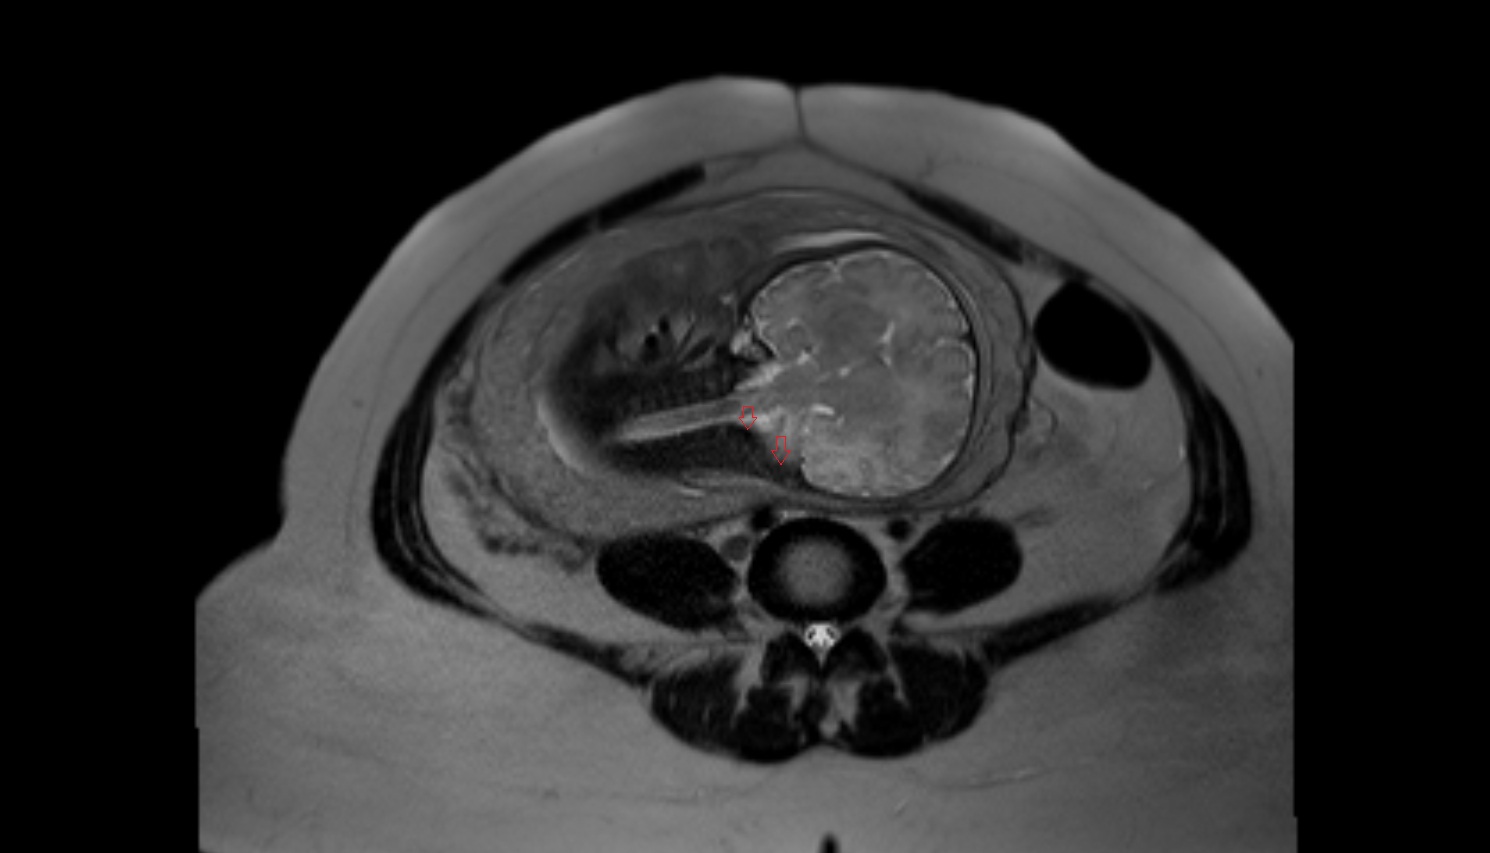

- Fetal brain

- Fetal caudate nucleus

- Fetal thalamus

- Fetal pons

- Fetal cerebellum

- Fetal occipital lobe

- Fetal temporal lobe

- Fetal parietal lobe

- Fetal frontal lobe

- Fetal third ventricle

- Fetal fourth ventricle

- Fetal lateral ventricle